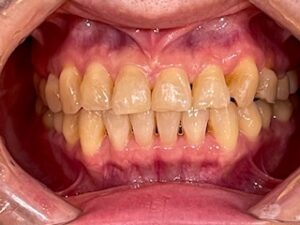

■治療後の状態

(after1.jpg)

治療後は、前歯の重なりが解消され、自然で美しい歯並びになりました。歯列が整ったことで、見た目の印象が大きく改善されただけでなく、歯磨きもしやすくなっています。

患者様からも「もっと早くやればよかった」とご満足のお声をいただきました。